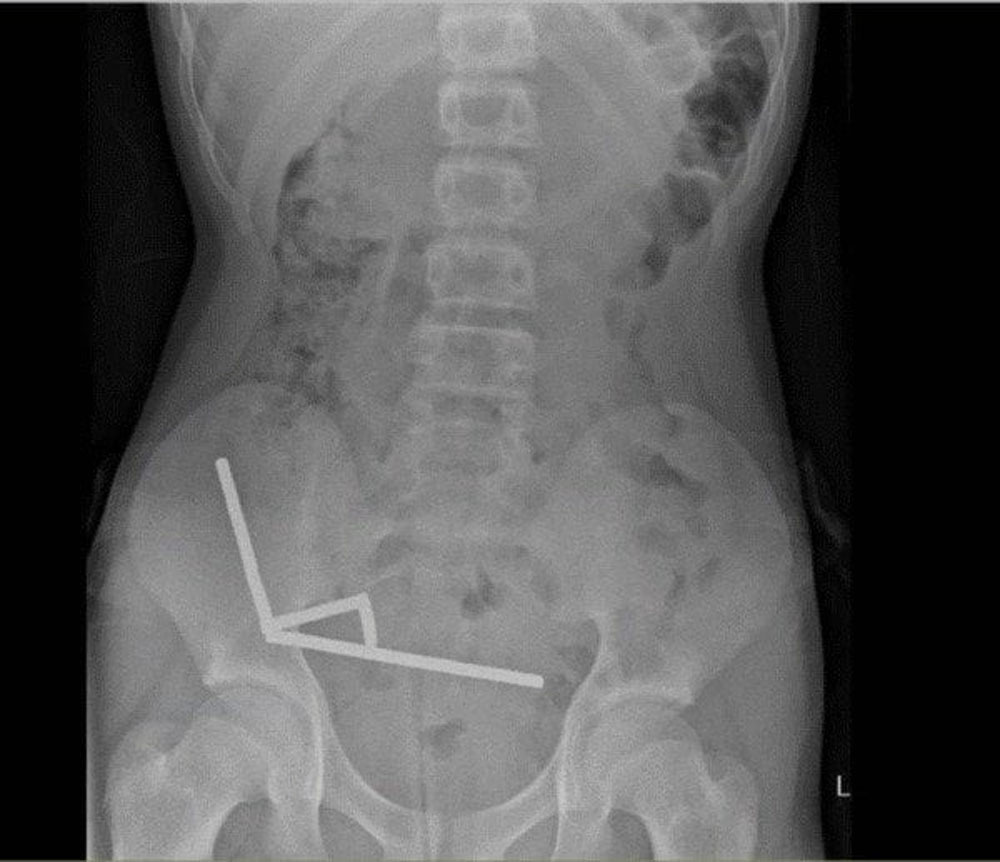

Paauglys medikams prisipažino, kad prieš savaitę prarijo, kaip manė, apie 100 magnetų. Vėliau rentgeno nuotrauka parodė, kad jo žarnyne susidarė keturios linijinės grandinės. Šie magnetai, susijungę per žarnyno sieneles, suspaudė audinius ir sukėlė nekrozę – audinių apmirimą dėl kraujo trūkumo.